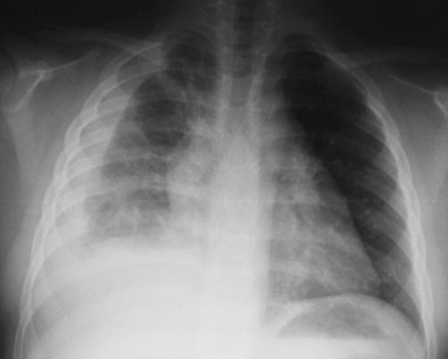

节段性肺炎

(segment pneumonia)

5 岁男孩患节段性肺炎

胸部 X 线检查 :见左中

肺野羽毛 状阴影(箭头)